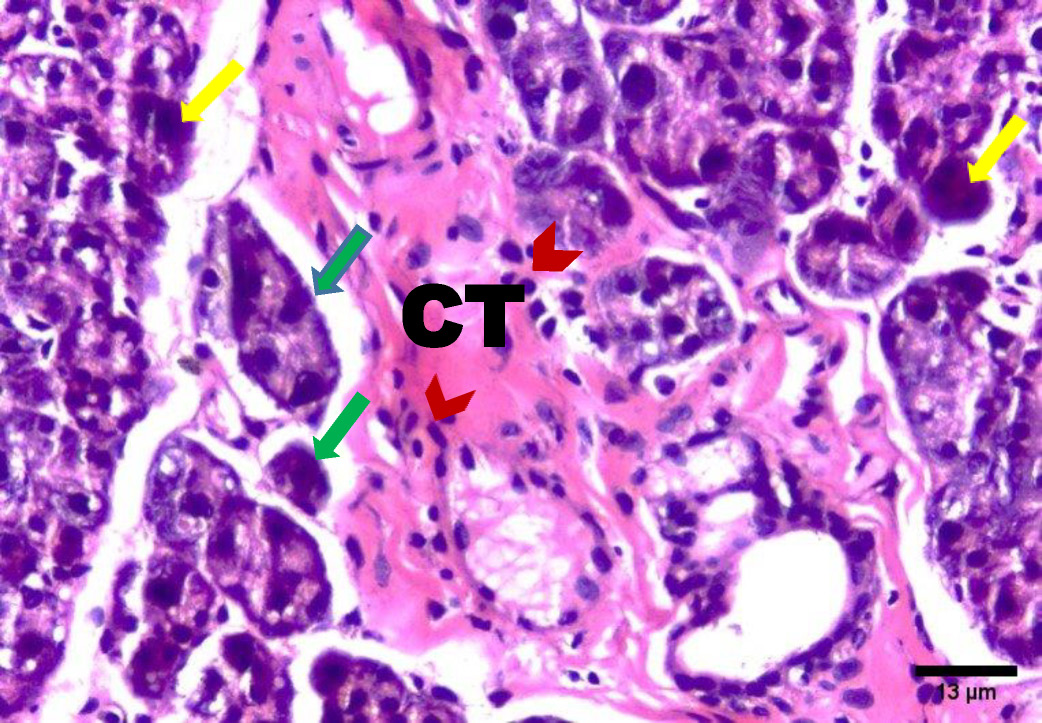

The H&E stained sections of group A (irradiated only) showed degenerative changes at both day 14 and day 30. Acinar shrinkage, multiple cytoplasmic vacuoles and nuclear anisonucleosis and poikilonucleosis were detected. The duct system showed thinning of the epithelial lining of some excretory ducts and stagnant secretion was found in others. Both intercalated and striated ducts showed no detectable changes. Areas of fibrosis were detected in the connective tissue that was chronically infiltrated by inflammatory cells. Additionally, the blood vessels suffered from dilatation and some appeared engorged with RBCs. Also, some blood vessels showed hyalinization and others were ruptured (Figure 2, Figure 3).

The results of the present study showed acinar degeneration, shrinkage and cytoplasmic vacuolization in group A (day 14 and day 30). Boraks, Tampelini, Pereira, and Chopard have linked acinar degeneration and vacuolization to the expansion of the endoplasmic reticulum which is associated with the cellular status that precedes apoptosis this expansion is related to compression of the nuclear material.19

Moreover, the observed nuclear changes (anisonucleosis & poikilonucleosis) and clumped acini with condensed chromatin reported in this work are in agreement with Krishnan et al. who observed shrunken nuclei with condensed chromatin in irradiated salivary gland acinar cells. The author assumed that the irradiation dose was not high enough to cause complete DNA destruction and complete nuclear disintegration.21

In the present investigation, excretory ducts showed degeneration of their lining, others showed stagnant secretion in group A (after 14 days). These findings corroborate with those reported by Kassab, and Tawfik who detected degeneration of excretory duct and stagnant secretion due to oxidative stresses and inflammation in albino rats subjected to long term use of caffeinated drinks.23

In this study, the stagnant secretion found in some excretory ducts in group A was previously shown by Halawa, Mohamed, and Obeid who found some dilated excretory duct with stagnant secretion and concluded that the mitochondrion is the most vulnerable cell organelle to toxic agents and oxidative stresses. Upon mitochondrial destruction in excretory ducts, cellular metabolism was affected with advanced cellular destruction. Destructed mitochondria result in adenosine triphosphate ATP consumption and subsequently, impaired exocytosis took place, so no energy for secretion causing stagnant secretion and ductal dilatation.24

In the current work, connective tissue fibrosis was noted mainly in group A (day 14 and day 30), consistent with Huang, Chen, and Miao who demonstrated that the connective tissue stroma of parotid and submandibular gland of rats undergoes adiposis and fibrosis after irradiation.25

The presence of blood vessels engorged with red blood cells was observed in this investigation in group A (14 and 30 days) which decreased in group B (14 & 30 days). These findings were in agreement with the results of Redman who found thinning and discontinuity in the endothelium lining of blood vessels of the parotid salivary gland of rats that was subjected to irradiation, leading to a compromised blood supply.26

Chronic inflammatory cells infiltration in the connective tissue in this study were clearly observed in group A (day 14 & day 30), replicating findings by Limesand, Said, and Anderson, who found chronic inflammatory cells in response to irradiation of parotid salivary glands of rats.27